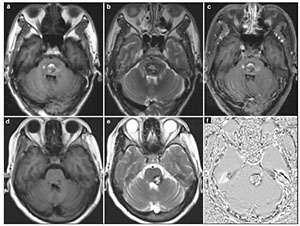

20170712151327 Figure 1 MRI demonstrated the typical “porpcorn” or “mulberry-like” BSCMs. (a), (b) and (c) showed one patient with pontine cavernoma. (d), (e) and (f) showed another patient with left cerebellar peduncle cavernoma. (a) and (d) axial T1-weighted, (b) and (e) axial T2-weighted, (c) axial enhanced T1-weighted, (f) SWI.